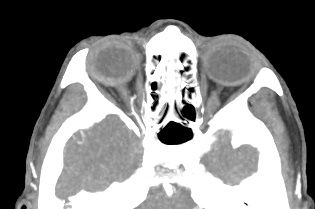

Для более детальной визуализации мягких тканей глазниц дополнительно применяется контрастное усиление. Для этого пациенту внутривенно вводится йодсодержащий контрастный препарат, благодаря которому становятся видны патологические образования размером до 1 мм. Методика позволяет обнаружить патологию еще до появления симптомов заболевания, когда лечение наиболее эффективно.

Новейшее оборудование наших медицинских центров представлено современными мультиспиральными компьютерными томографами экспертного класса TOSHIBA AQUILION. Различные версии аппаратов способны выполнять одновременно множество тончайших срезов исследуемой зоны. Благодаря этому получаются детальные изображения высокого качества за несколько секунд. Толщина срезов при этом составляет от 0,5 мм, что позволяет выявить патологические процессы на самых ранних стадиях развития, тем самым повысить шансы больного на успешное лечение.

На снимках КТ хорошо видны костные структуры глазниц, глазные яблоки, ретробульбарная клетчатка, слезные железы, канальцы, слезные мешки, носослезные каналы.

Мультиспиральная КТ с контрастом позволяет выявить: